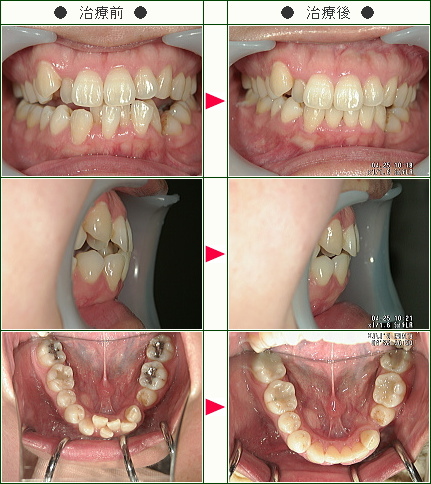

☆デコボコ症例(Yuriyuri様 47歳 女性)

▼患者様の感想

治療期間が短くて済んだ事は良かったです。

何より担当の先生が分かりやすく説明をして下さり、不安要素を取り除いて下さったことで期間を通して安心して治療を受ける事が出来ました。

仕上がりも美しく治療を受けて良かったです。

ありがとうございました。

今後ともよろしくお願い致します。

☆デコボコ症例(高橋様 48歳 男性)

▼患者様の感想

治療期間、特にブラケットを設置している期間が短かったので大変満足しています。

想像以上に治療を要する虫歯があり、今回その治療もすべて行うことが出来たので良かったです。